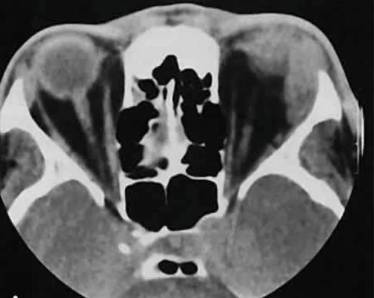

Диагностика:

- лабораторные исследования крови и тканей из ран;

- рентгенологическое исследование позвоночника;

- МРТ;

- КТ.